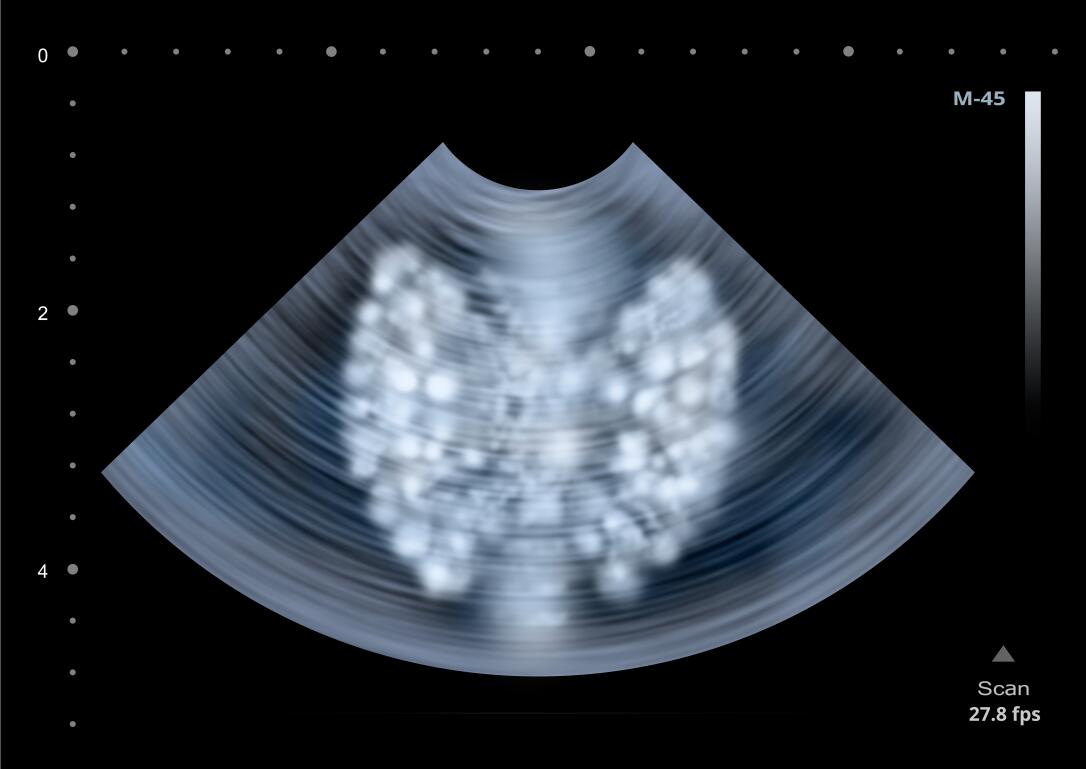

不过今天不谈疫情,我们来聊一聊长期发热警惕亚急性甲状腺炎。老王最近间断发热两个月了,吃饭不舒服,咽喉疼痛,在当地医院做了好多项目也查不清楚,转到上级医院后,内分泌科医生一摸脖子患者有痛感,进而做了甲状腺功能检查和甲状腺B超,最终被确诊为亚急性甲状腺炎。

亚急性甲状腺炎期间,甲状腺功能会有三种变化,首先是甲状腺毒症期,其次是甲减期,最后是恢复期。但是甲状腺的摄碘率会从甲状腺摄碘率减退逐渐恢复到摄碘率正常,因此亚急性甲状腺炎的病人,检查时不仅需要检测甲状腺功能,还需要做甲状腺的扫描和吸碘率,同时还要测血常规和血沉。

第二、患者甲状腺轻度到中度肿大,质地硬、触痛明显。